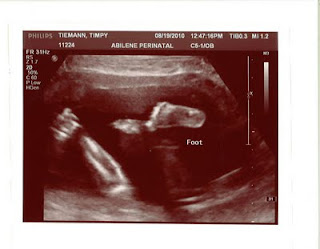

Today we had our 20 week sonogram.  This was Jacob's first time to go to the dr. with me. We patiently sat in the waiting room for our name to be called. Previously, we had talked about finding out the sex of the baby and we both agreed that yes, we want to know. Some one even asked Jacob what he wanted the baby to be and his response was, "...worse case scenario, it's a girl, and I can live with that."  I thought really.  What in the world are we gonna do if this baby is a girl?

Our name was finally called.  As we now sat in the examination room with monitors all around us, the thought crept into my mind.  Do we really want to know. Quickly, I reminded myself -- YES! I need to know what bedding to buy. I didn't want to have an all yellow and green room.

Once the technician came in, she turned out the lights and turned on the monitors.  She asked us if we wanted to know the sex and we both looked at each other and simultaneously said, "Yes."  She said ok and proceeded to put goopy cold stuff on my belly.  She picked up the wand and pressed it to my belly.

If we didn't want to know the sex of the baby, we would have been disappointed because as soon as she pressed the wand to the right side of my belly, there were all his man parts.  Before she said anything, Jacob said, "That looks like a boy."  She said, "Yep, that's a boy." and continued to move the wand around his boy parts checking them out and then moved on to his legs and arms and head and then his heart.

It was so amazing to not only see his tiny heart beating, but to hear it too. WOW! that is something really amazing. She took a few pictures along the way and then the dr. came in to tell us that according to the sonogram we have a happy healthy baby boy at 20 weeks 4 days. What a relief!

Healthy, and everything was measuring the right length, width. He has arms and legs and a brain -- and they are all the right size.  Such a relief to know that.  Now if I can only start feeling better.